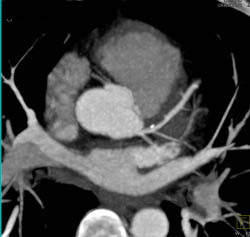

Diagnosis

Plaque in LAD